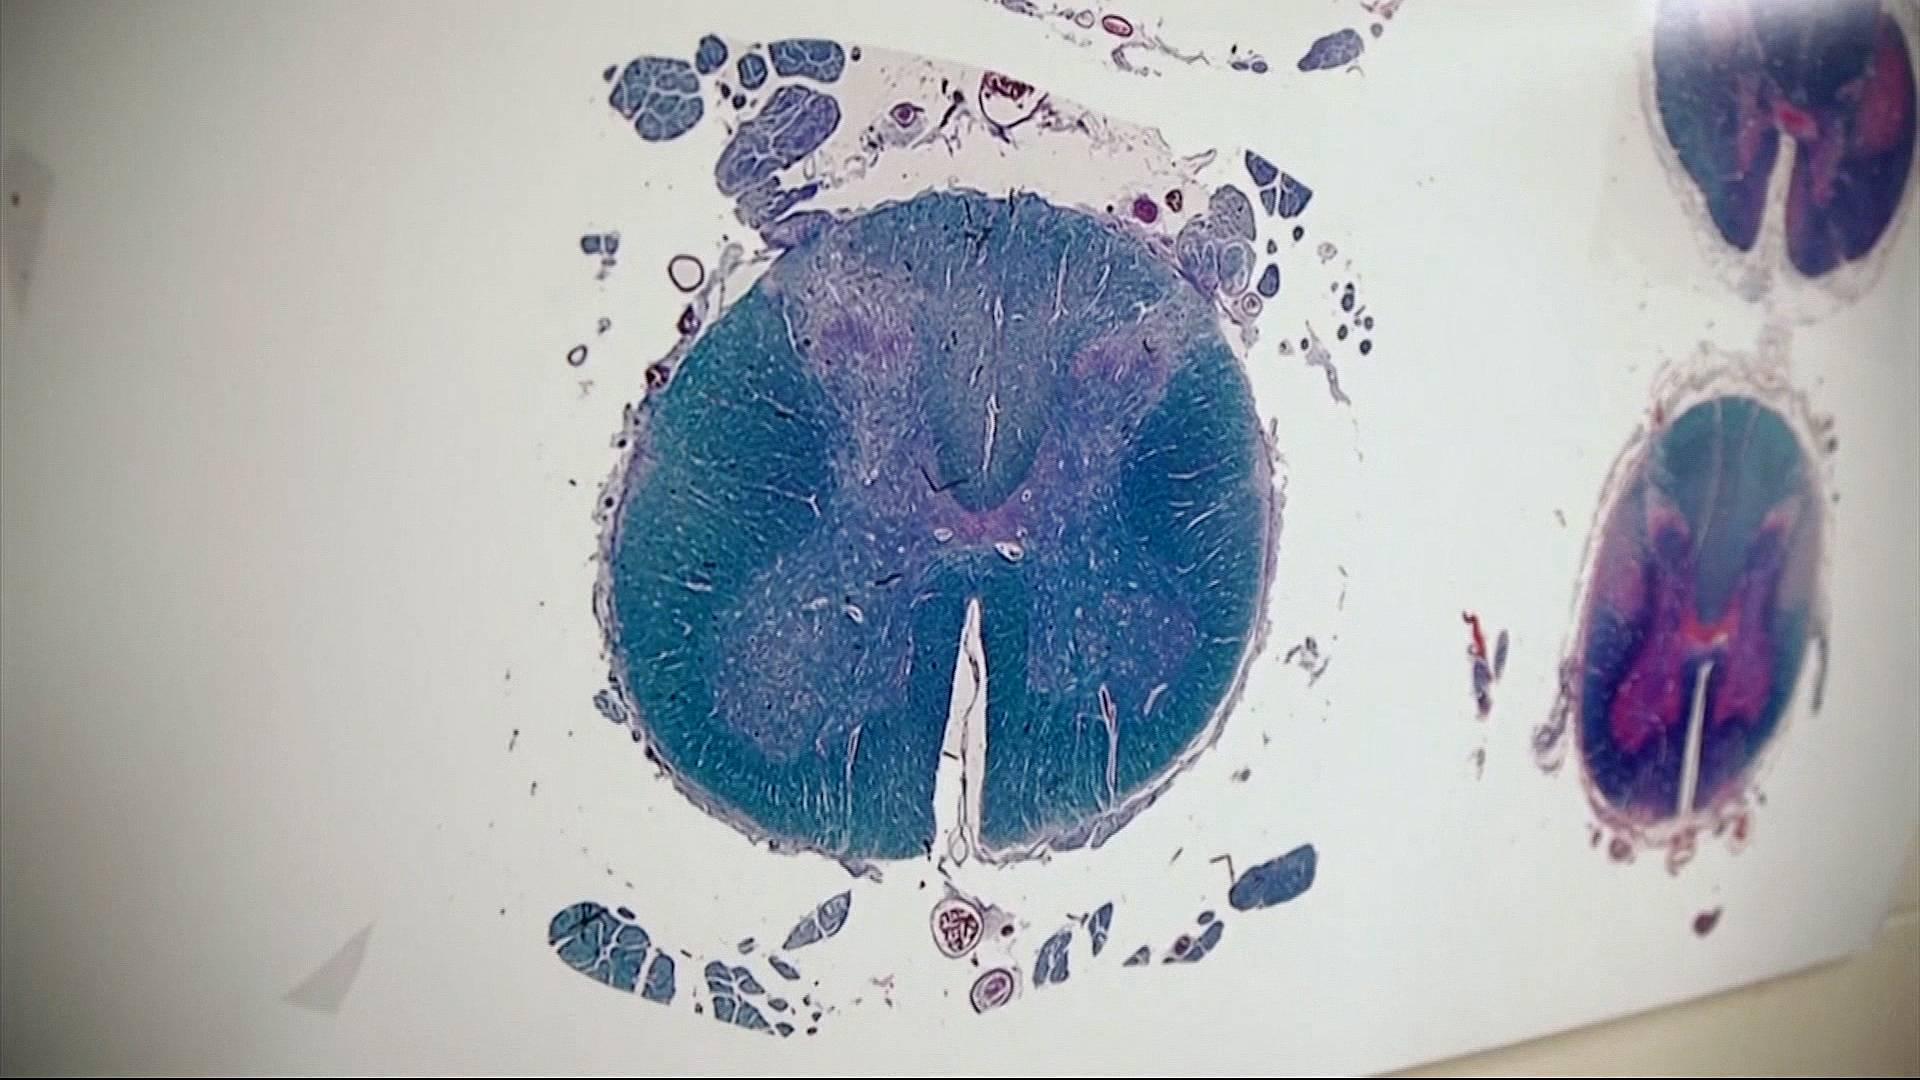

Post-mortem examinations of more than 200 former NFL players found that nearly 99 percent revealed signs of a disease linked with repeated blows to the head.